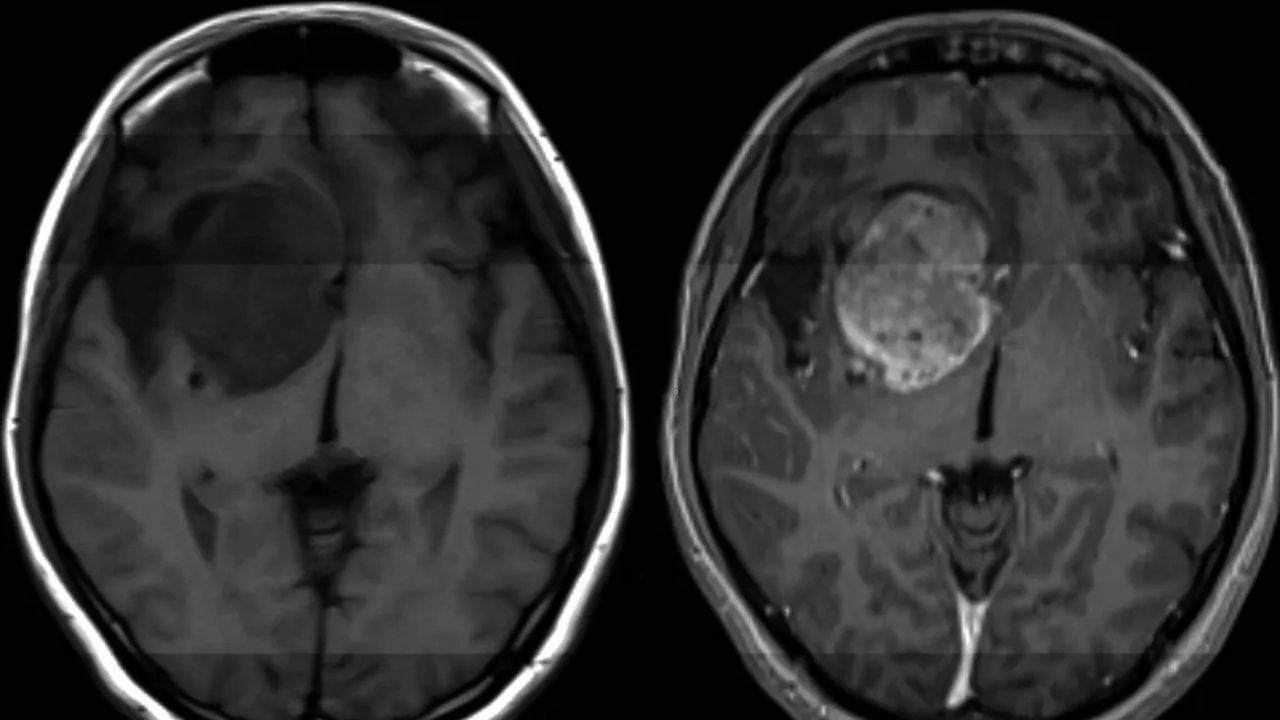

Glioblastom, tıbbın bugün hâlâ etkili bir çözüm üretemediği en yıkıcı kanser türlerinden biri olarak biliniyor. ABD’de her yıl on binlerce kişiye bu tanı konulurken, hastaların büyük bölümü tanıdan sonra yalnızca 12–18 ay yaşayabiliyor. Şimdi ise bilim insanları, bu tabloyu değiştirebilecek yeni bir biyolojik zayıf noktaya ulaştıklarını duyurdu.

Ekip, son çalışmada söz konusu onkogenin faaliyetini durdurabilen özel bir molekül tanımladı. Fareler üzerinde yapılan deneylerde bu molekülün, sağlıklı beyin dokusuna zarar vermeden glioblastom hücrelerini yok ettiği görüldü. Araştırmacılar, bu yaklaşımın bugüne kadar tedavide kullanılmamış tamamen yeni bir biyolojik yolak hedeflediğini belirtiyor.

Glioblastom tedavisinin önündeki en büyük engellerden biri, ilaçların kan-beyin bariyerini geçememesi. Ancak bu yeni molekülün, bariyeri aşabildiği ve yalnızca kanserli hücreleri etkilediği ifade ediliyor. Bu özellik, yöntemi mevcut yaklaşımlardan ayıran en önemli unsur olarak öne çıkıyor.